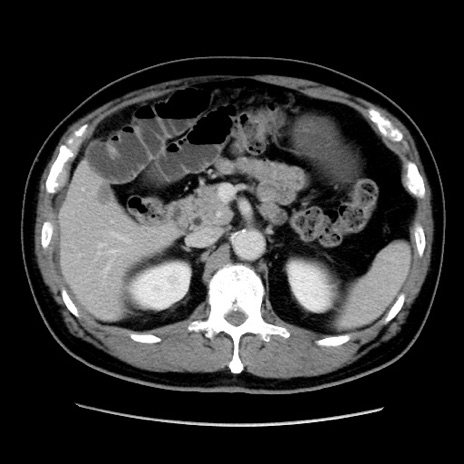

症例16(横断像)

【症例】 70歳代男性

【主訴】 腹痛、嘔吐

【現病歴】 約1ヶ月前より間欠的に腹痛と嘔吐あり、当院消化器内科を受診したところCTで多発する肝臓のLDAを指摘され、精査中であった。以降は消化器症状は安定していたが、2日前より嘔気と腹痛があり、同日より排便・排ガスが消失した。改善認めず、 本日、救急外来を受診した。

【既往歴】 大腸ポリープ切除後。

【身体所見】意識清明・会話良好、BT 36.3℃、BP 127/80mmHg、 P 80bpm、腹部:膨満あり、平坦・軟、上腹部正中および下腹部正中に圧痛あり、反跳痛なし、筋性防御なし。

【データ】WBC 7200、CRP 0.77